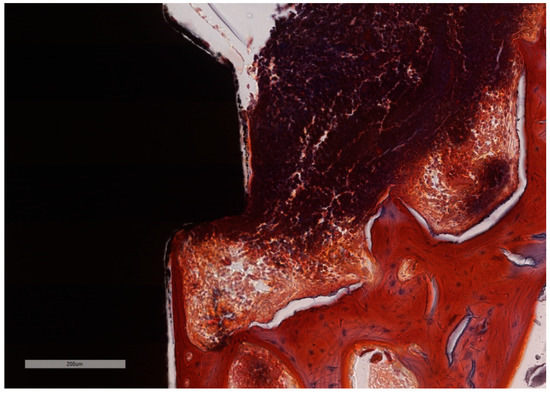

Figure 8. “Open wound” aspect of the ICT in contact with the implants surface and a total lack of the epithelial lining. ICT is diffusely present in the soft tissue and is seen to progress into the bone marrow, without any sign of fibrous encasement. The peri-implant sulcus is deep and the intimate contact between the soft tissues and the implant is below the BC level (implant #3, MGA, bar measure is 900 µm).

Figure 10. In the absence of the ligature, full epithelial lining is observed along the interface with the implant, with no ulceration. Note the intimate contact between the soft tissues and implant surface that coronally ends above the level of the BC, while the ICT remains above the BC-BD line. (implant #2, MGA, bar measure is 700 µm).

The histological assessment of the processed specimens showed the partial osseointegration of the implants in all cases. Implant and screw integrity, along with the persistence of ligatures was observed in specimens 1, 3 and 5. The bone height level was lower on the buccal aspect than on the oral aspect, the difference being bigger in the specimens with experimentally induced peri-implantitis. The peri-implant sulcus is deeper in all ligated specimens than in non-ligated ones (Figure 8 and Figure 9), and the intimate contact line between the soft tissues and the implant is seen only below the level of the BC. Epithelial lining integrity (as seen in Figure 10) was broken in several places in 2/3 of implants with ligation and in ½ of the implants without ligation, more pronounced on the oral aspect (Figure 11). In these areas of integrity loss, the inflammatory cells were identified in direct contact with the implant (Figure 12 and Figure 13). In ligated specimens, the ligatures were seen partly covered in two thirds of the cases by the soft tissues, while in one third of the implants, in the oral aspect, the ligatures were identified as below the level of the PM. The infiltration of the bone was seen in all cases of ligation and in half of the implants without ligation. In all implants, ICT was mostly composed of inflammatory cells (lymphocytes and plasma cells, with scattered neutrophils) separated by hyperemic blood vessels and a network of sparse collagen fibers. At implant No. 4, although the ICT seemed to be partially surrounded by dense collagen bundles, the deeper infiltration of the bone marrow by ICT was observed.